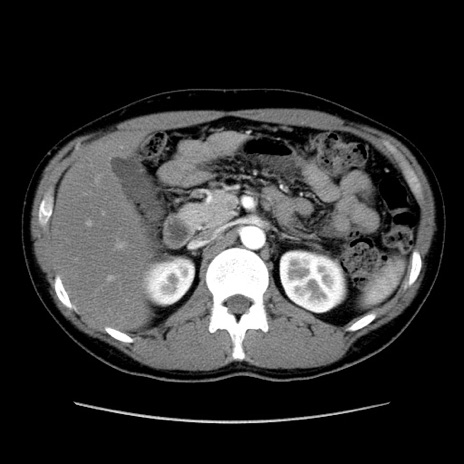

冠状断像

【症例】20歳代 男性

【主訴】心窩部痛

【現病歴】今朝より上腹部痛あり。一旦軽快していたが再度出現したため救急要請。昨日夕に白身の魚を含む刺身を食べた。

【身体所見】BP 136/89mmHg、HR 74/min、BT 37.0℃、腹部:膨満、軟、心窩部に圧痛あり。反跳痛なし、筋性防御なし、腸雑音やや亢進あり。

【データ】WBC 17700、CRP 0.48